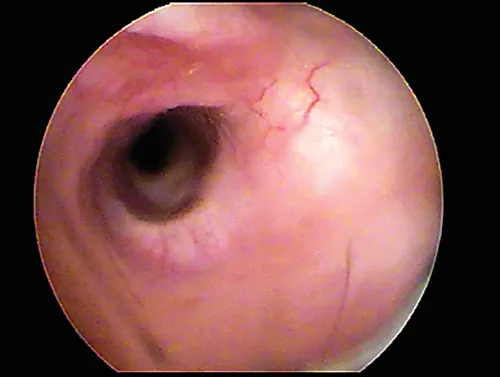

Otoscopic image of pink mass with red striping seen behind ear drum.

FIGURE 15

Tissue mass behind the eardrum. Note the malleus bone in the pars tensa, indicating the mass is behind the eardrum.

The eardrum may be opaque from chronic inflammation and thickening and/or hyperkeratosis. If the eardrum is opaque, the middle ear cannot be evaluated visually from the ear canal.

In some dogs, the pars flaccida of the eardrum may be bulging from fluid pressure in the middle ear behind it (Figure 16) and may obscure visualization of the pars tensa. Some have suggested that this enlargement may be caused by degranulation of mast cells and resultant edema from atopic dermatitis.7,8 This condition is frequently mistaken for a mass in the external canal and should be closely evaluated.